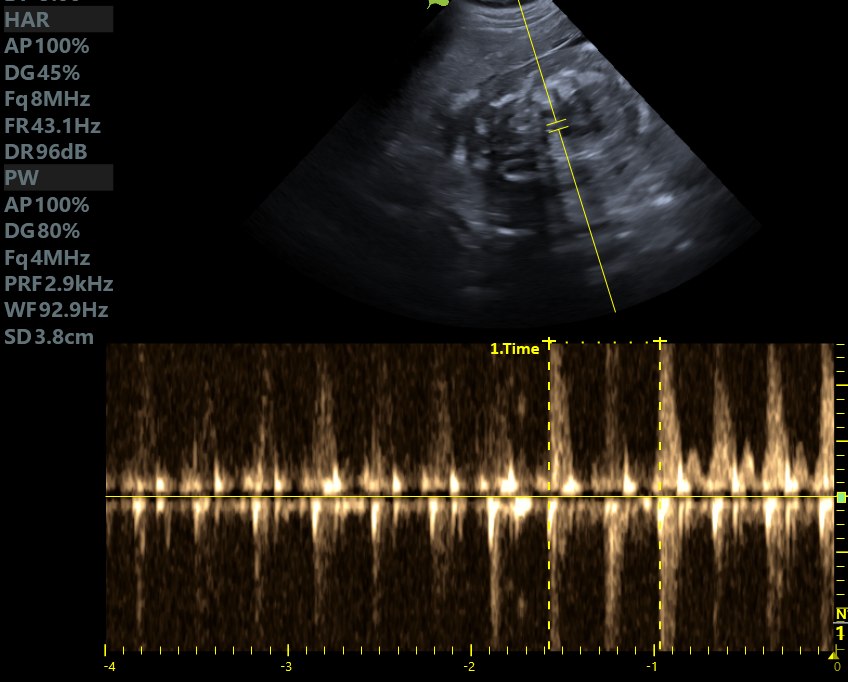

Kontrolne badanie USG pacjentki Weterynarii Dobieszowice. Serduszka biją prawidłowo, poród tuż tuż…..